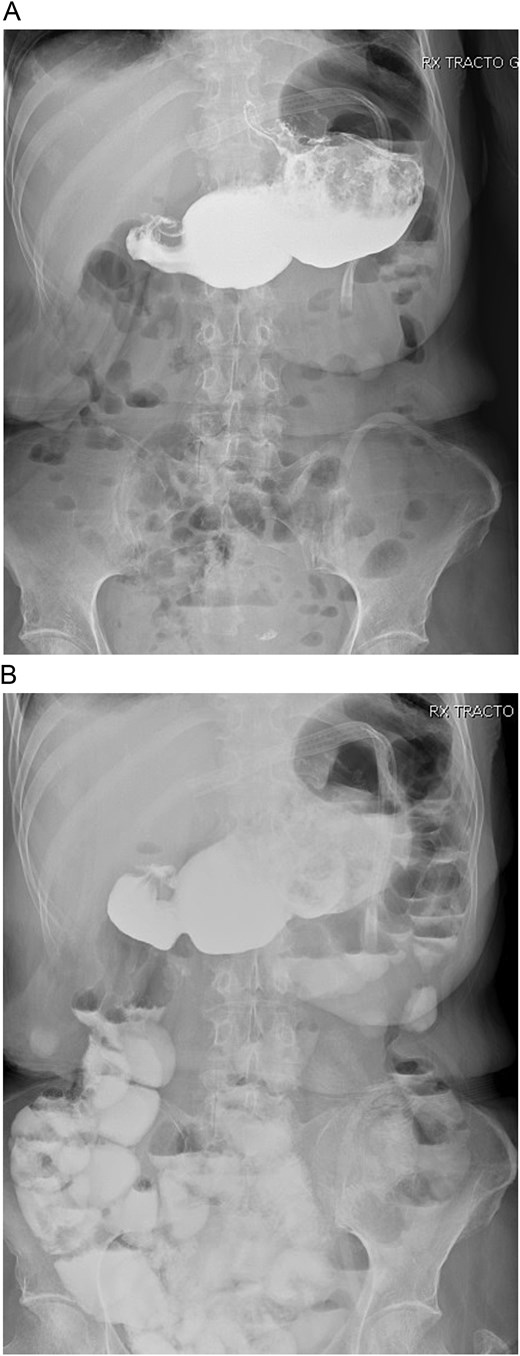

With these findings, a bypass reversal was decided. The alimentary limb was resected from the jejunal-jejunal anastomosis using mechanical staplers (Endo GIA 60 mm purple, COVIDIEN, North Haven, CT, USA), and a latero-lateral gastrostomy was performed between the gastric pouch and the gastric remnant without complications. A drain was placed after a negative methylene blue test, and surgery was completed without complications. Clear liquids were initiated on the first postoperative day without difficulties, and a new bowel transit time was done, which revealed no leaks and that the contrast reached the colon in 10 hours (Fig. 2A and 2B).

A: Bowel transit time, the whole stomach is seen connected. B: Bowel transit time, the whole stomach is seen along with the bowel.